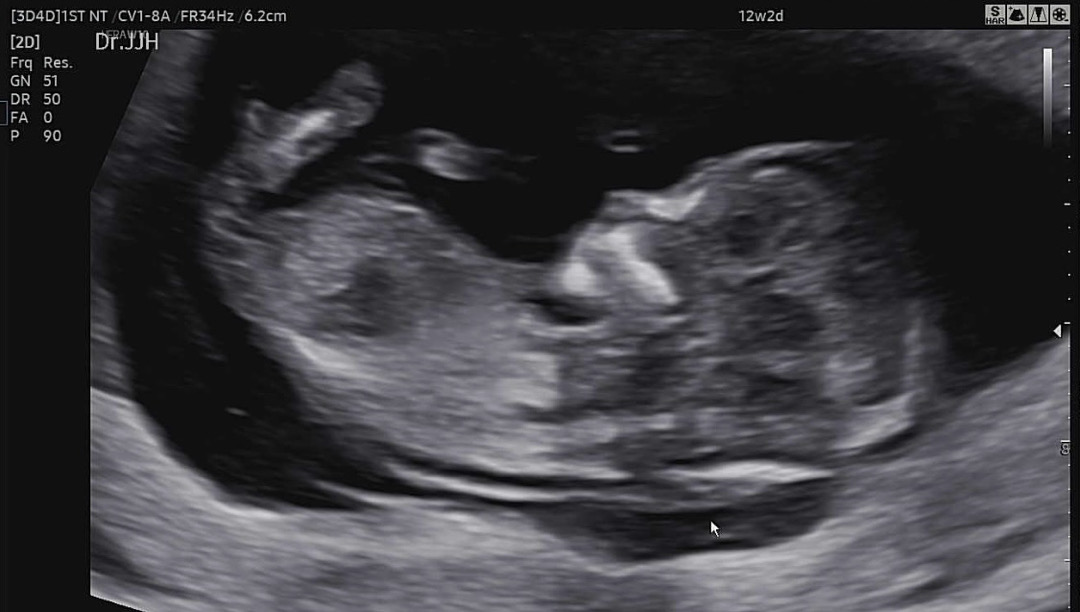

12주2일 각도법 봐주세요!!

각도법 부탁드립니다~!!

딸같은데요?